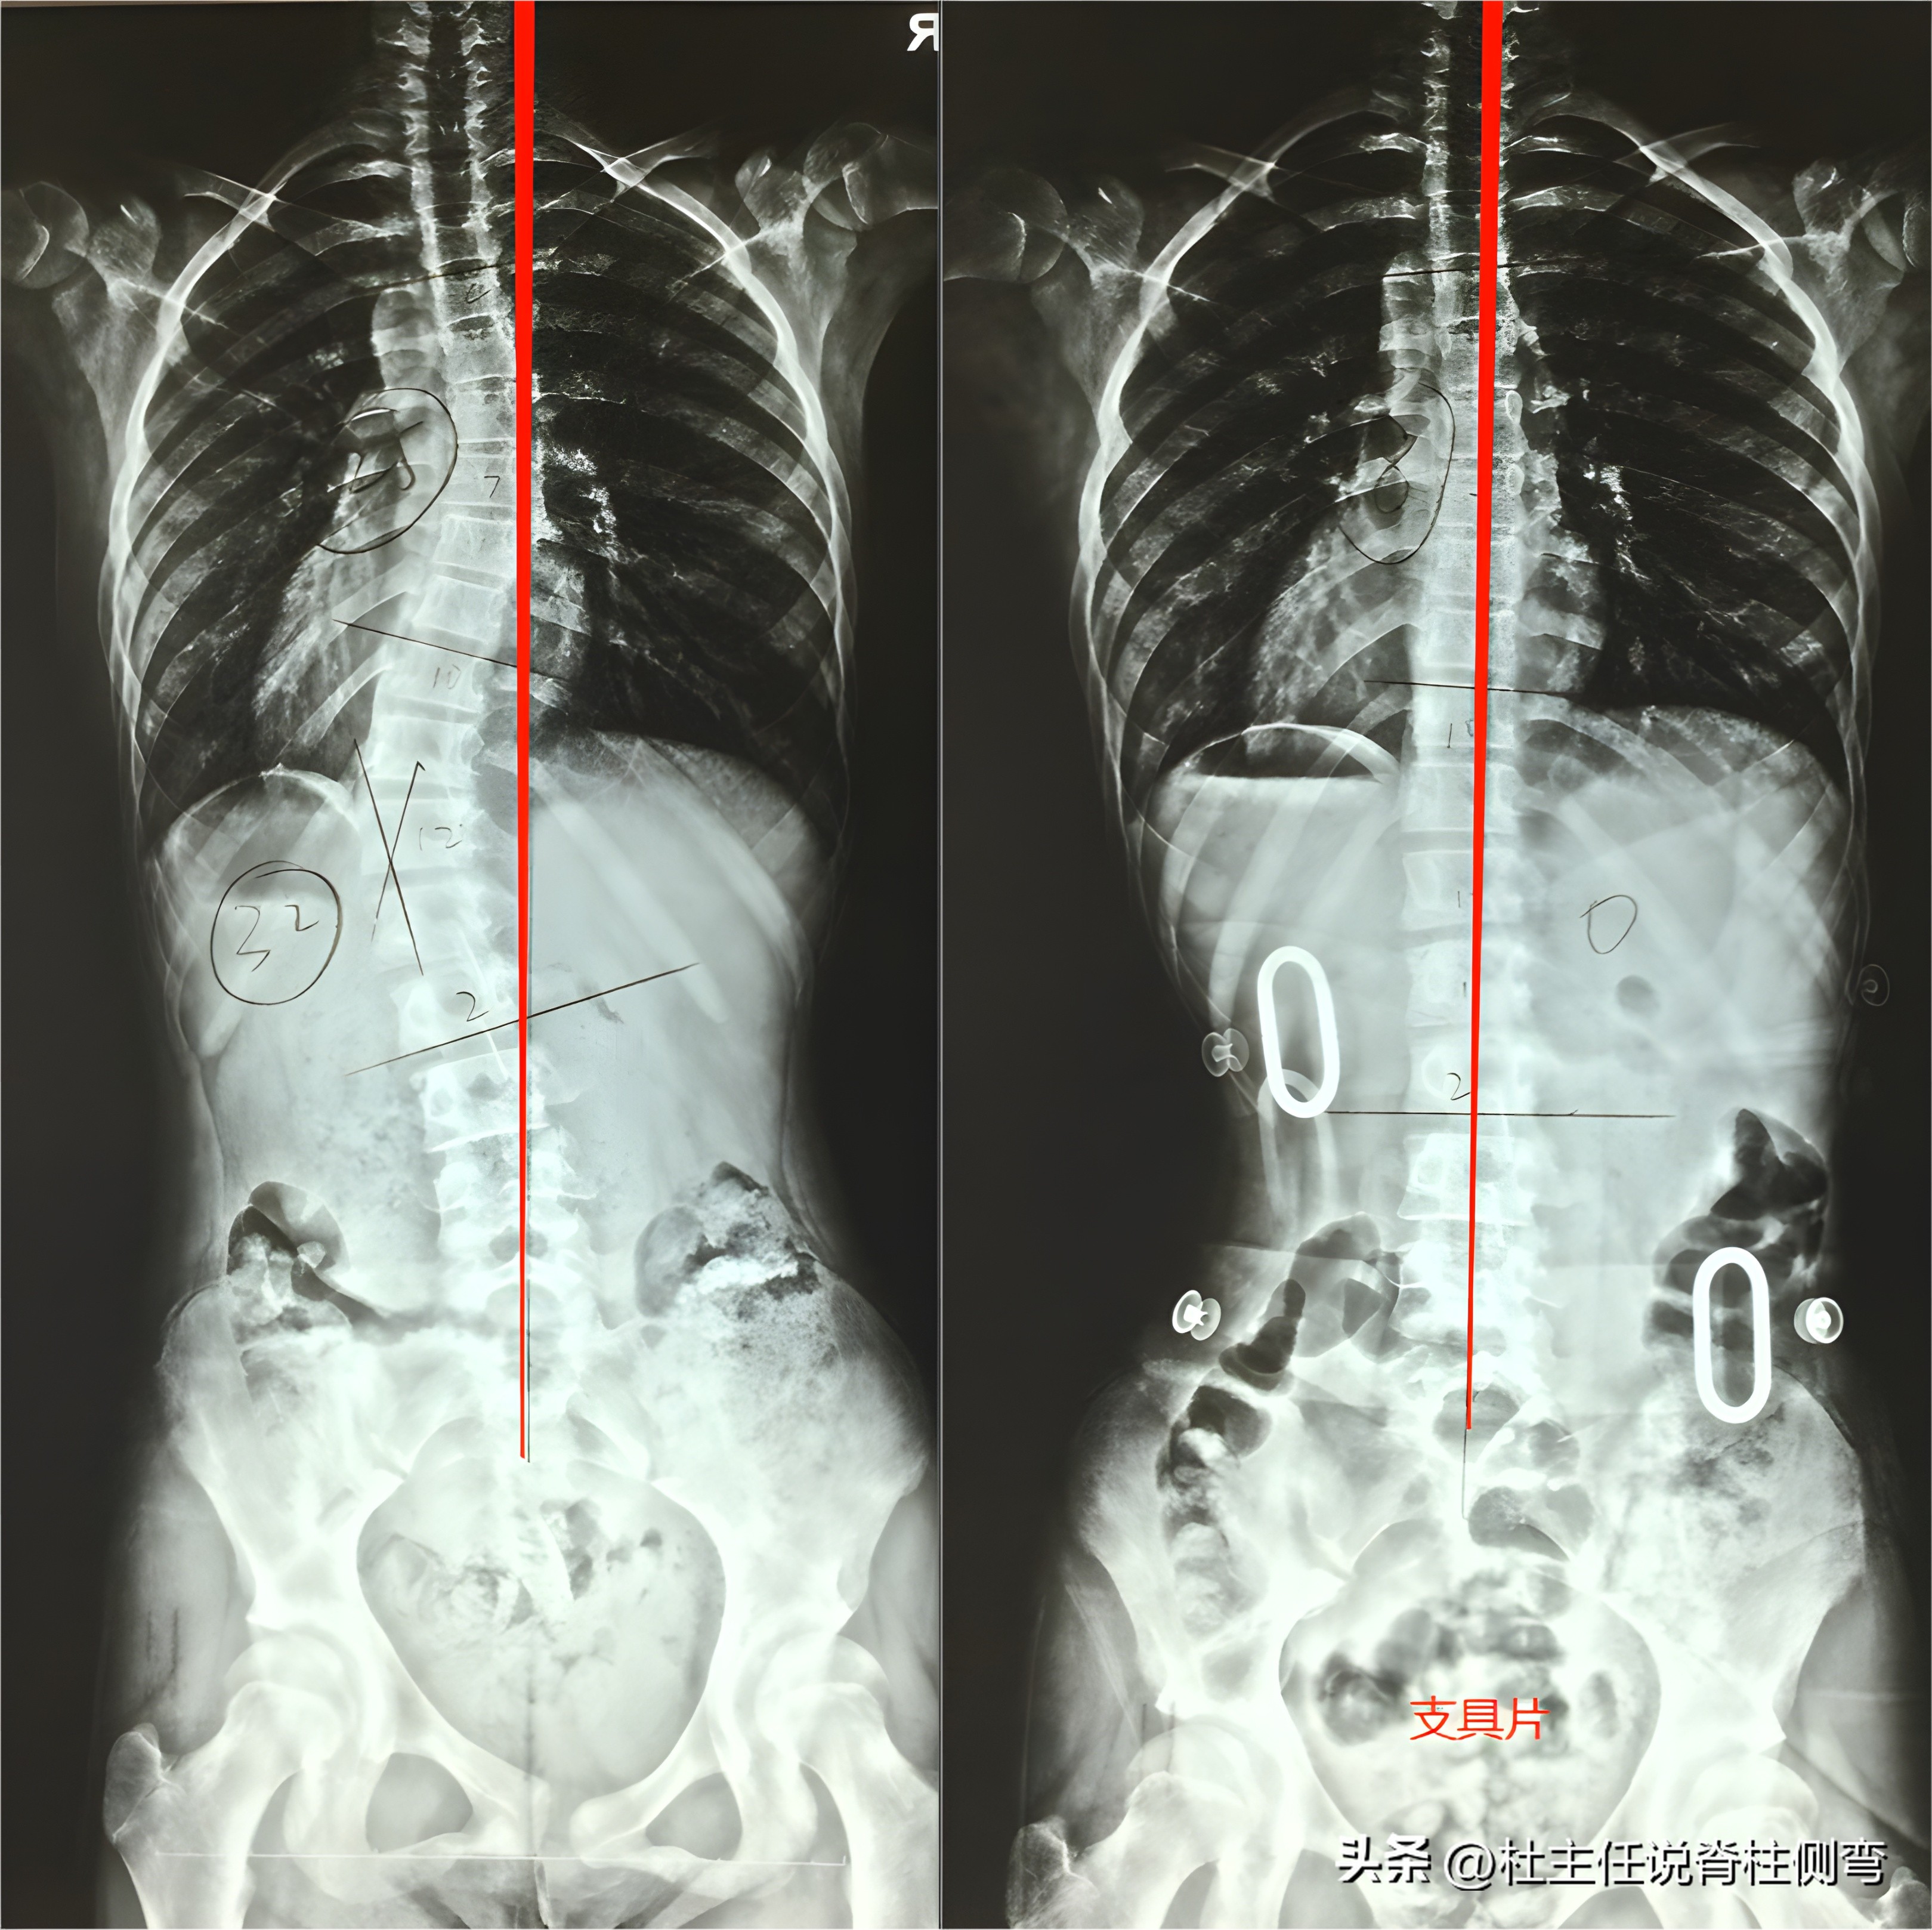

在8月份,找到龙脊康门诊希望做进一步诊治。孩子的X光片显示,以T7为中心向右侧凸, Cobb角约24° ,以L1为中心向左侧凸, Cobb角约30° ,Risser征:2级,脊柱整体向中线左侧偏移。

于是,我们给孩子定制了 腰弯短支具 。支具下拍片显示,以T7为中心向右侧凸, Cobb角约8° ,以L1为中心向左侧凸, Cobb角约0° ,支具矫形效果很好。